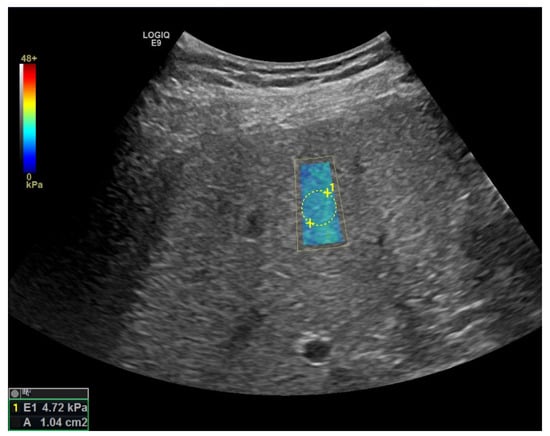

Elastography

| pSWE [41] | F ≥ 2: 69% F ≥ 3: 80% F = 4: 76% | F ≥ 2: 85% F ≥ 3: 86% F = 4: 88% | -integrated in high-end devices, performing in combination with regular US | -smaller ROI |

| 2D-SWE [41] | F ≥ 2: 71% F ≥ 3: 72% F = 4: 78% | F ≥ 2: 67% F ≥ 3: 72% F = 4: 84% | -integrated in high-end devices, performing in combination with regular US -larger ROI (potential more representative) | -high failure rate in obese patients -lack of studies for most devices -lack of defined quality criteria |